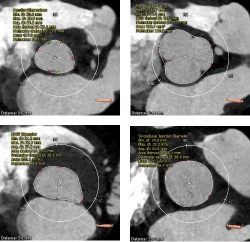

CT结果显示,患者为三叶式主动脉瓣,轻度钙化,瓣叶明显增生肥厚但未见明显融合,结合瓣上结构和左室流出道结构特点,较大可能影响瓣膜植入后的形态及贴壁性,存在瓣膜向下位移的风险,且大概率需要使用瓣中瓣策略完成手术。在瓣膜尺寸的选择上要更为精准,在瓣膜释放时,释放位置更要把握好。该患者还存在弓部夹角锐利,弓部宽度较短,且降主动脉扭曲,极大地考验了器械输送系统的过弓性能。

三叶式主动脉瓣, 瓣叶明显增厚,未见明显融合粘连,瓣叶钙化较低,假体瓣膜锚定难度较高,存在瓣膜位移风险,瓣中瓣风险偏高。

主动脉根部评估

冠脉阻挡风险评估

瓣环上解剖结构评估